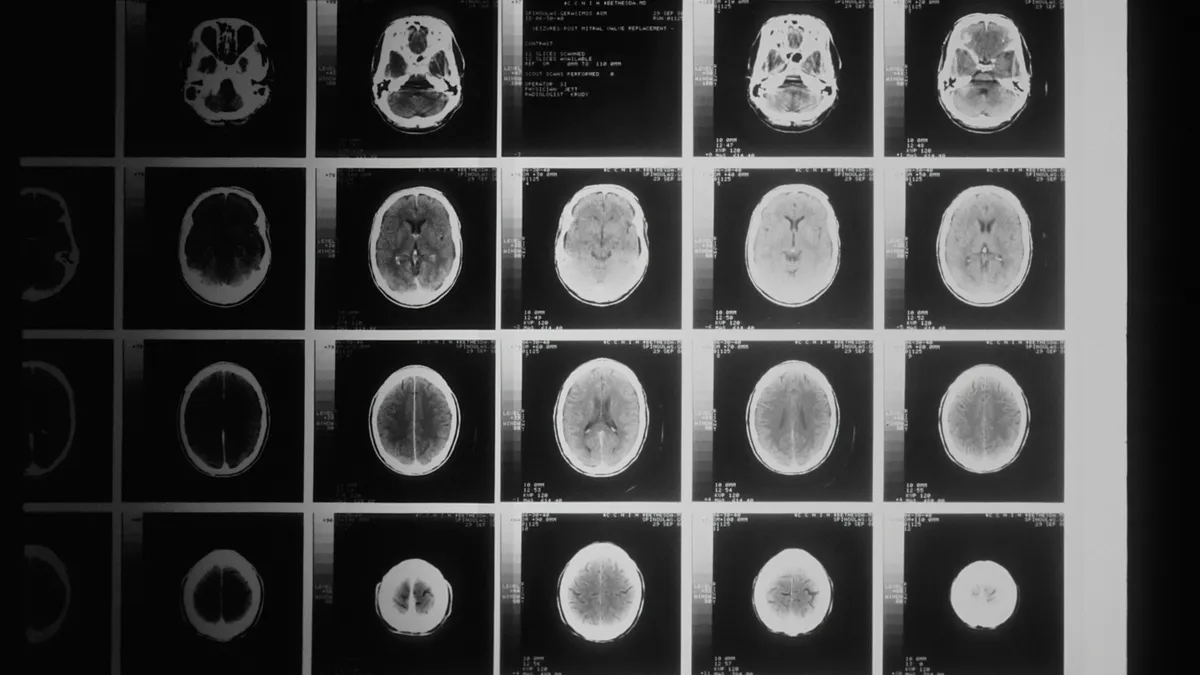

Az azt megelőző napokban a férfi már érzett egy szokatlan zsibbadást a végtagjaiban, de nem tulajdonított neki nagy jelentőséget. Ugyanebben az évben július óta éles fejfájások és rohamok is gyötörték, és már várt egy MRI-vizsgálatra. Mindezek ellenére, amikor közölték vele a sztrók után, hogy glioblasztómája, az agydaganatok legagresszívabb formájával küzd, teljesen ledöbbent.

Bár a cardiffi Walesi Egyetemi Kórház sebészei 2023-ban el tudták távolítani a daganatot, az azóta visszanőtt.

A júliusi MRI kiújulást mutatott, ezért további három kemoterápiás kezelést kaptam. A bal karom ismét leállt... A novemberi MRI megerősítette, hogy a kemoterápia nem volt hatásos, és a daganat tovább növekszik. Gyógymód nincs, a kezelési lehetőségek pedig korlátozottak, így nem tudom, mit hoz a jövő.